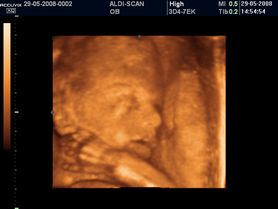

Zdjęcia płodu

Zdjęcia płodu - twarze

Płód w 40 tygodniu ciąży (zdjęcia 3D)

Płód w 34 tygodniu ciąży (zdjęcia 3D)